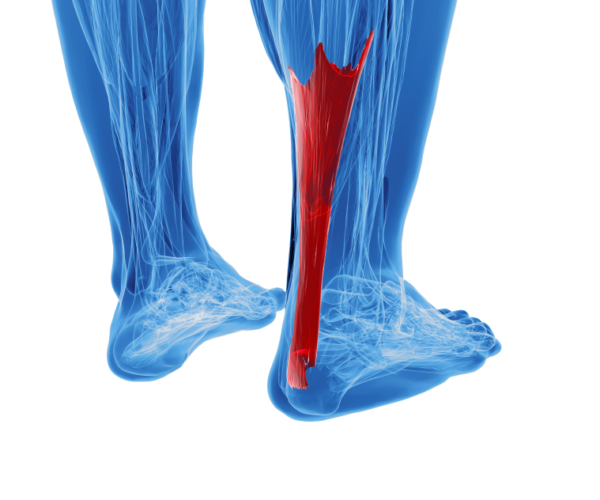

Tendinitis de Aquiles en tenis es una tendinopatía por sobreuso del tendón que une los gemelos con el talón. En tenis aparece por la suma de impactos en pista dura, arrancadas, frenadas, sprints y cambios bruscos de volumen de juego. Los síntomas típicos son dolor y rigidez en la parte posterior del tobillo, sobre todo al iniciar la actividad o al día siguiente de un partido intenso.

El tendón de Aquiles soporta cada impulso que haces para arrancar hacia la pelota, saltar a por el saque o frenar después de un sprint. En tenis esa exigencia se multiplica por los cambios de dirección constantes y las decenas de pequeños saltos que haces sin darte cuenta durante un partido.

Cuando la carga supera la capacidad del tendón, el tejido se irrita y empieza a doler. Al principio puede ser una simple rigidez matutina o una molestia al empezar a calentar, pero si sigues apretando igual, la tendinopatía se instala. Esa combinación de pista dura, poco trabajo de fuerza y decisiones de calendario arriesgadas es muy típica en jugadores de club.